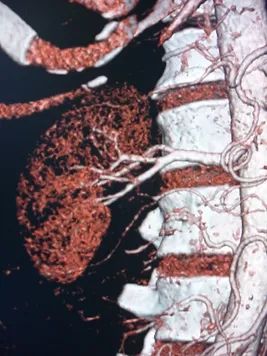

A hormone-secreting tumour that can occur in the adrenal glands. Phaeochromocytomas usually develop in the small glands on top of the kidneys (adrenal glands). They most commonly affect people between the ages of 20 and 50, but can occur at any age. Because of hormones secreted, symptoms include high blood pressure, sweating, rapid heartbeat and headache. Surgery to remove the tumour is usually required.